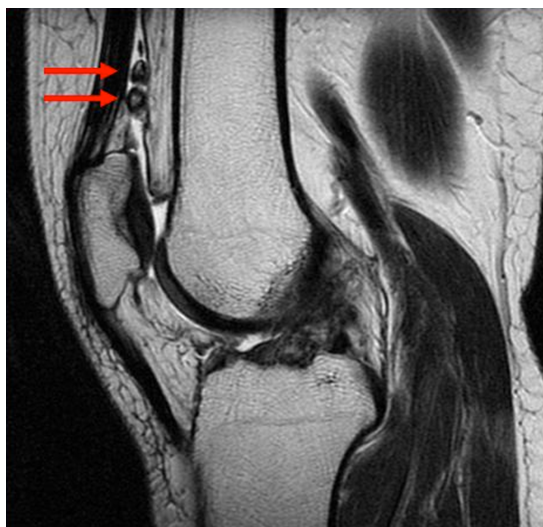

영상 진단: X-레이, MRI, CT 스캔을 통해 연골 종양을 확인할 수 있습니다.